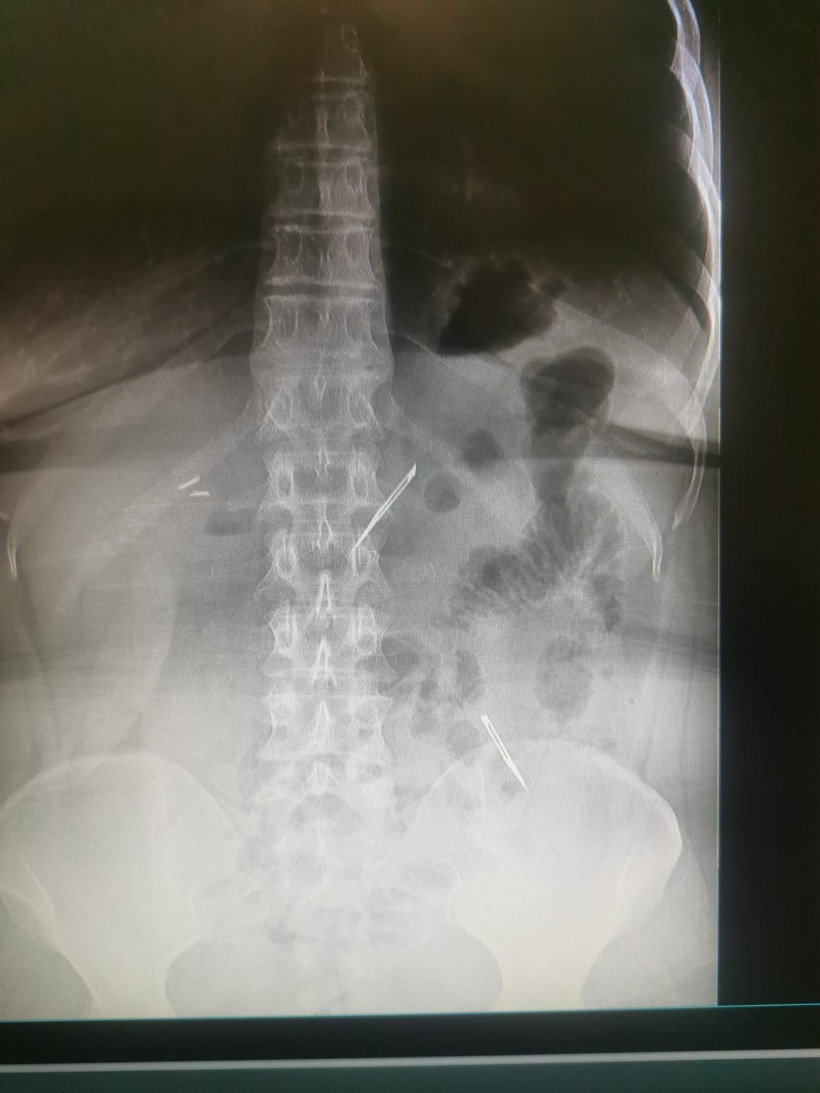

Sağlık Bilimleri Üniversitesi Ankara Atatürk Sanatoryum Eğitim ve Araştırma Hastanesi’ne mide ve karın bölgesinde aşırı ağrı şikayeti ile müracaat eden 46 yaşındaki D.E.’nin yapılan tahlil, tetkik ve çeşitli görüntülemelerden sonra bağırsak kısmında 2 adet neşter olduğu tespit edildi.

Hastanın şikayetlerinin artması üzerine gerçekleştirilen tetkiklerde 46 yaşındaki kadının karın bölgesinde 2 adet yabancı cisim olduğunu tespit ettiklerini, detaylı inceleme sonucunda bu cisimlerin neşter olduğunu fark ettiklerini belirten Prof. Dr. Buluş, “Yaklaşık 10 gün önce kliniğimize karın ağrısı ve bulantı şikayetleri ile başvurdu. Bizim yaptığımız fiziki muayene ve tetkiklerinde hastanın direkt karın grafisinde 2 adet yabancı cisim olduğunu tespit ettik.

Aslında yabancı cisim bizim güncel grafiğimizde sık karşılaştığımız bir durum değil, fakat nadir de olsa görebildiğimiz bir patoloji. Biz de bunun üzerine ayrıntılı değerlendirmeler ve tetkikler yaptık. Sonrasında 2 adet yabancı cismin bistüri (neşter) ile uyumlu olduğunu gördük. Bunun üzerine hastanın şikayetlerinin de artması üzerine, ameliyat kararı verdik.